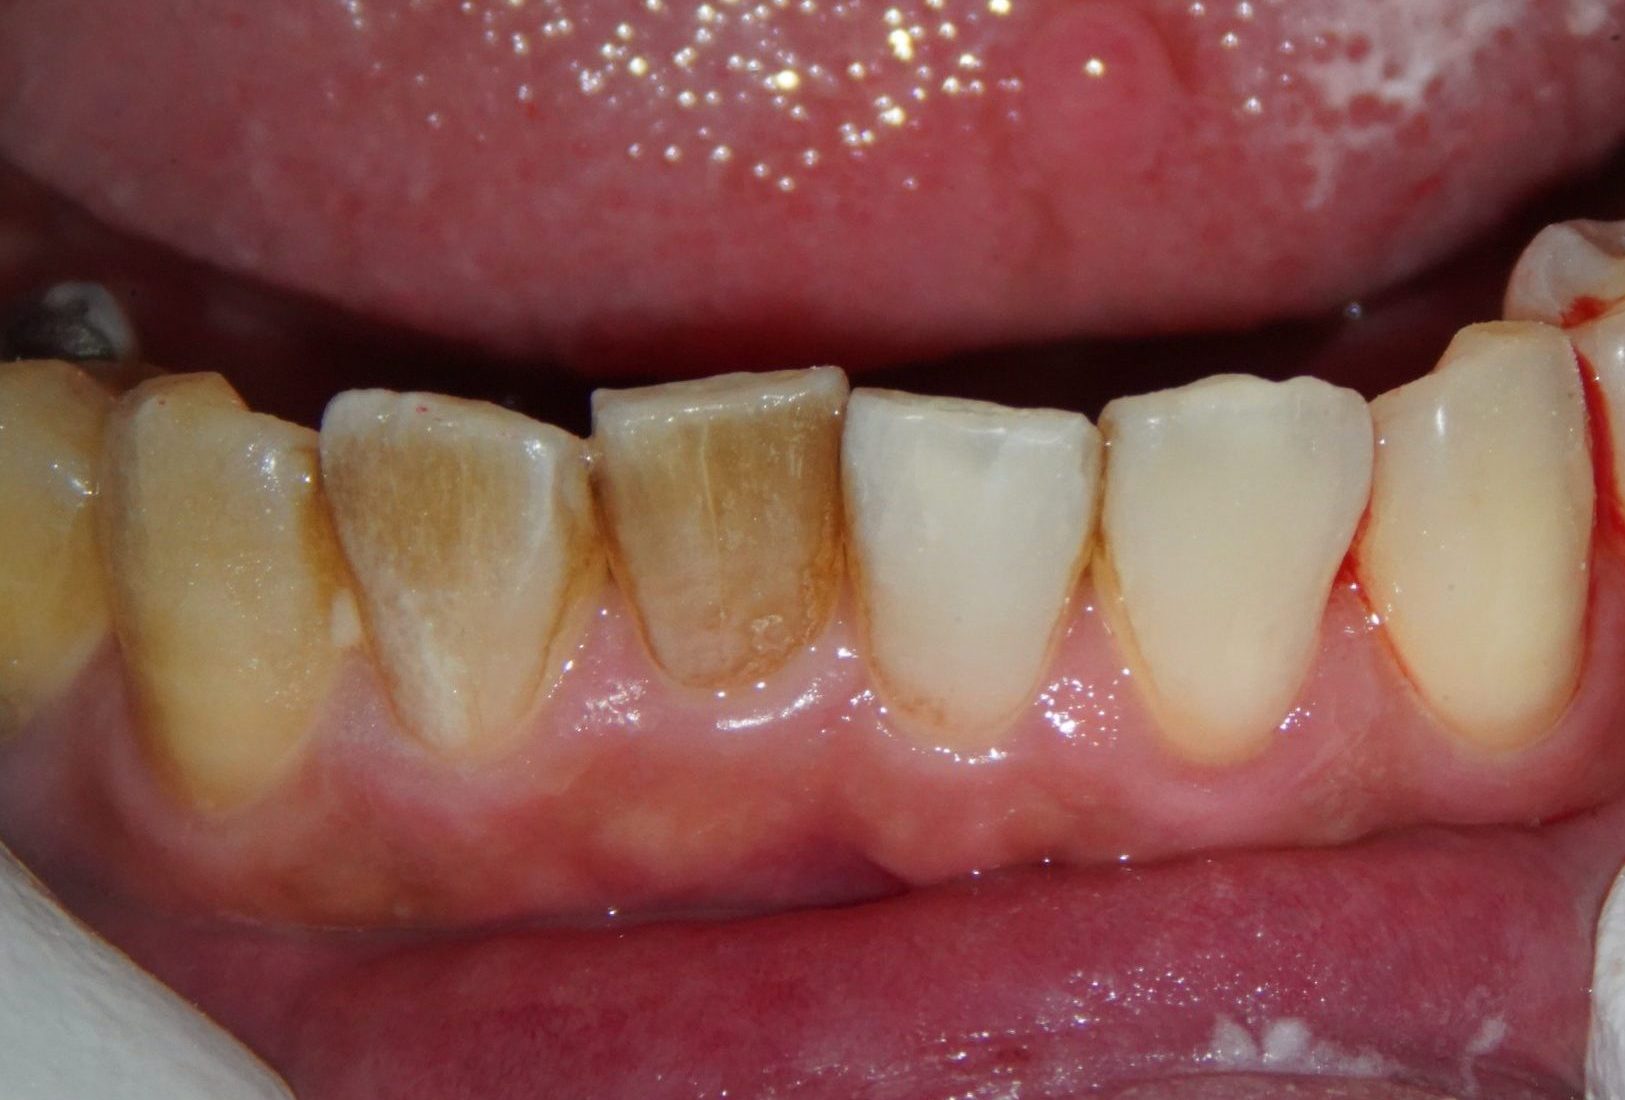

一般的な歯周病治療(保険診療)は、歯石除去や歯周ポケットの処置を複数回に分けて行うことが多く、治療期間が長くなりがちです。さらに歯周病は「サイレントディジーズ」とも呼ばれ、初期の段階では見た目の変化や痛みもありません。そのため歯周病治療はあまり重要視されず治療回数もかかるため通院が面倒となり途中でやめてしまう患者さんが大変多い印象です。そして症状が現れた時にはもう手遅れの状態で「抜歯」となってしまうのです。

パウダークリーニングは、微細なパウダーを水とともに噴射し、歯の表面だけでなく歯周ポケット内部に付着したバイオフィルム(細菌の膜)を効率よく除去できるクリーニング方法です。従来の器具による歯石除去だけでなく、器具が届きにくい部分まで清掃できるため、短時間で高い清掃効果が期待できます。着色(ステイン)も綺麗に落ちます。

パウダークリーニングの効果